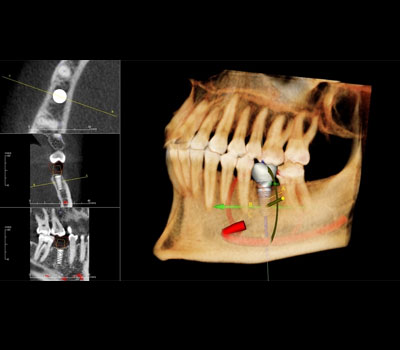

The Teeth-in-an-Hour™ protocol is a unique solution made possible by the ®System from Nobel Biocare, Sweden. A custom-made precision drill guide and a pre-fabricated prosthesis, based on CT images and virtual planning, can be made before surgery. All major decisions of the treatment are made during the software planning. The execution of the implant placement that follows is performed with minimal surgical intervention like flapless surgery.

The rapid development of computerized tomography (CT) scan techniques has made it possible to fully visualize the placement of implants in a real 3D environment before they are even placed, for their accuracy in final treatment.

The use of surgical templates to place implants has been shown to provide added value and surgical templates with high precision sleeves have optimized teeth rehabilitation since planning is both anatomically and final position of the teeth driven.